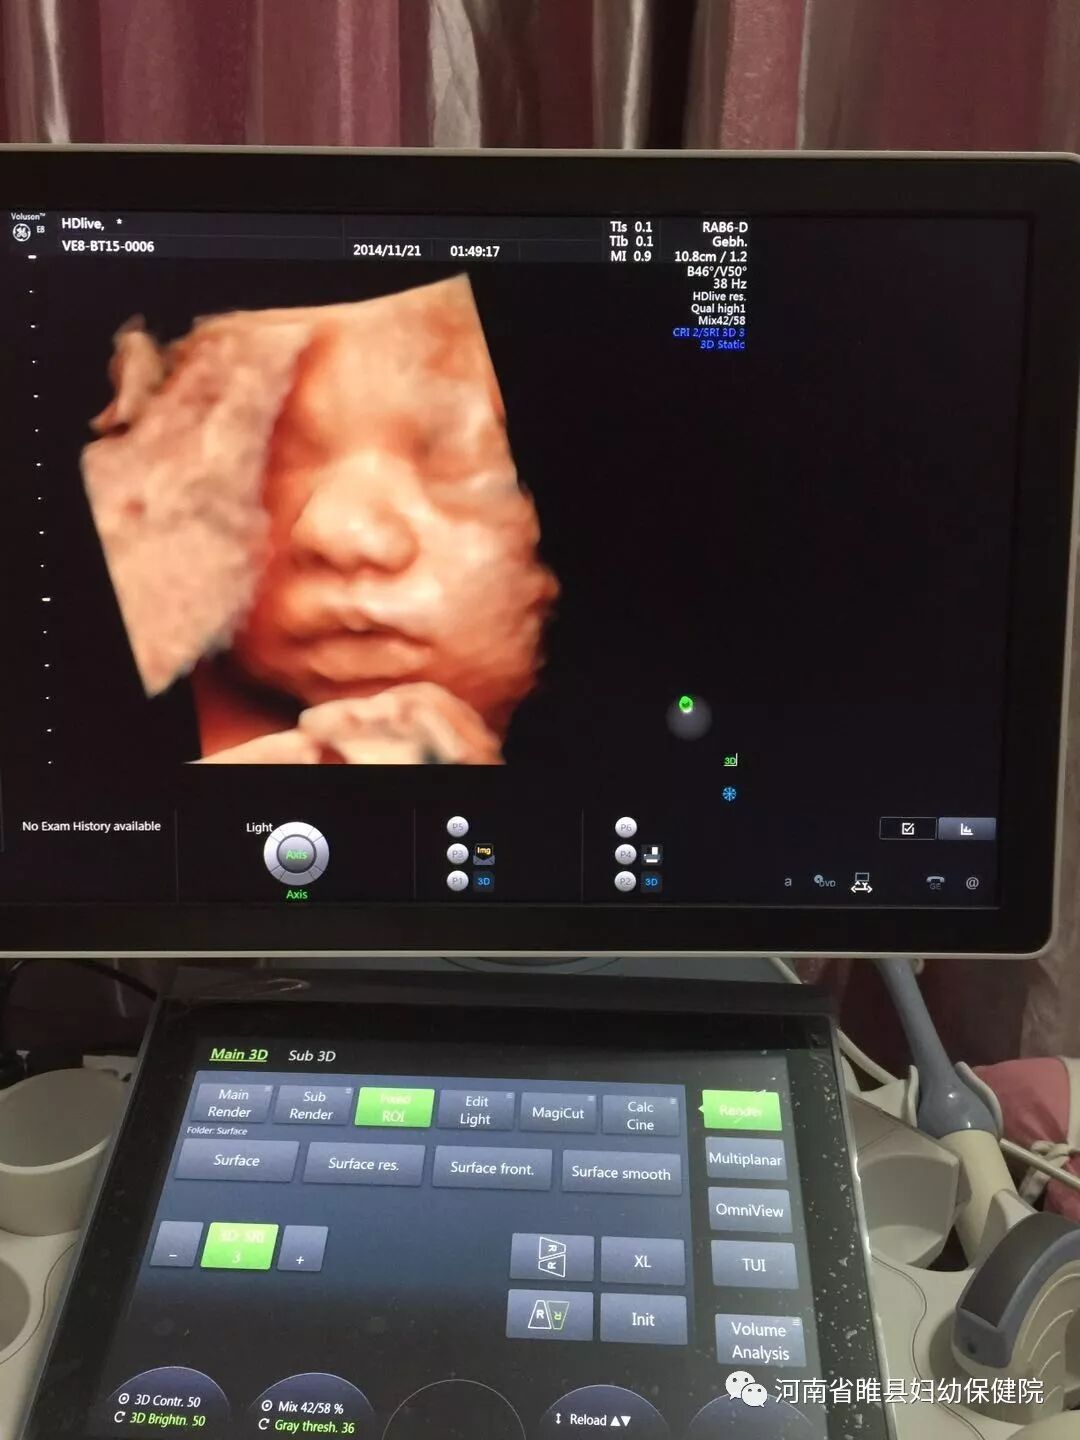

高科技让您看清宝宝最初的样子

美国新一代煊光GE-E8四维彩超,是目前国内功能最全、分辨率最好的四维超声技术,具有高清晰度、高分辨率、高精确度,高成像速度及对血流信号的高敏感性,能多方位、多角度观察胎儿生长发育情况,为早期诊断胎儿体表及内脏的多种先天性畸形提供准确的影像依据,是其它彩超无法比拟的;同时,其出色的人体工程学设计,不存在射线、光波和电磁波等的辐射,让广大的准妈妈安心,放心。

四维彩超堪称胎儿健康的“保护神”,作为新一代的四维彩超,煊光Voluson E8更先进的技术为孕妈妈提供了更高品质的服务,煊光Voluson E8四维彩超的清晰度无可比拟,对于普通四维彩超其可以给出更有价值的诊断。

它拥有10种4D着色图和独有的“透明模式”功能,能模拟子宫内的色彩。360°立体成像层次感和分辨率更高,彩超室内还配置了超大显示屏,准妈咪妈躺着就能观看到一部记录生命最初感动的4D大片。